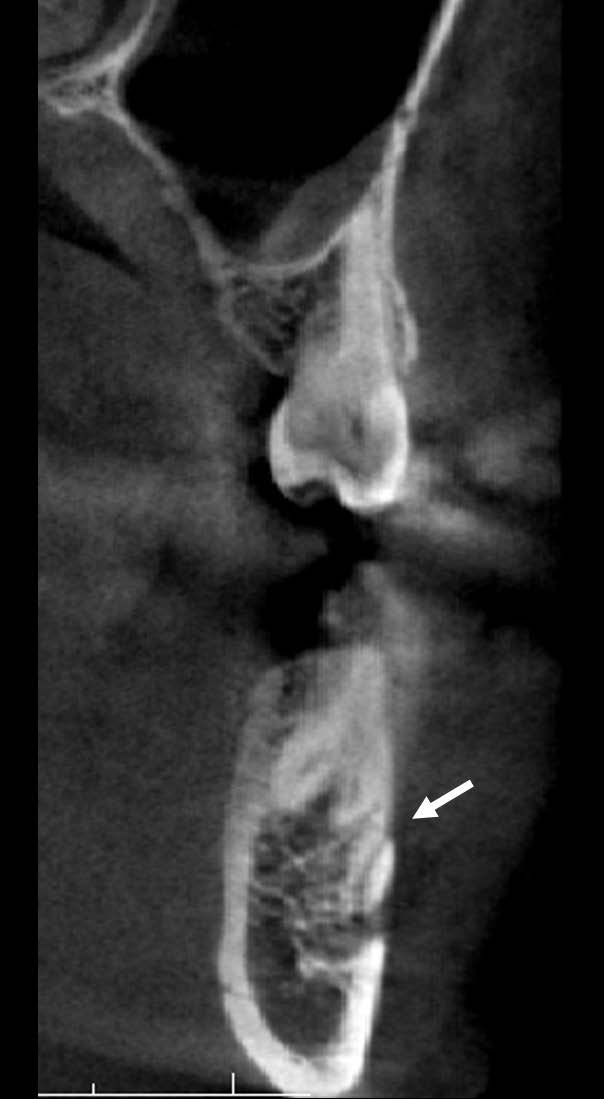

Es posible también encontrar más forámenes, a éstas foraminas adicionales se les denomina foramen mentoniano accesorio (FMA). Es importante distinguir entre un FMA y un foramen nutricio (2). Un FMA verdadero parte del CDI, mientras que un foramen nutricio, si bien aporta nutrientes a la mandíbula, no tiene comunicación con el CDI (6).

El FM es un hito anatómico a través del cual emergen el nervio mentoniano y su paquete vascular, su posición y forma varían mucho en la literatura (1,5). Es posible encontrar más forámenes en la zona, estos se llamarán FMA si se comprueba su continuidad con el conducto mentoniano o con el CDI, y se llamarán FLL si emergen en la superficie lingual distal a la zona de caninos y se continúan con el CDI. Si estos forámenes extras no presentan una continuidad con el CDI o con el conducto mentoniano, se les denominará foramen nutricio (14, 16). Su detección es de gran importancia en el planeamiento de diversos tratamientos para evitar disturbios sensoriales y accidentes, ya que la injuria de un foramen con más de 1 mm de diámetro puede causar una hemorragia importante (16,17), por ello el propósito de este estudio fue evaluar la posición, forma y variantes anatómicas del foramen mentoniano.

La frecuencia de los FMA reportada en la literatura varía mucho, desde 1,76% (13) hasta 55% (1), además de la diversidad étnica, esta variación puede deberse a diferencias en la metodología y en la definición de los FMA. El uso de las imágenes renderizadas no es metodológicamente correcto para el estudio de los FMA, ya que un foramen menor de 1.3 mm2 no se detectará fácilmente (6), además que no nos permiten descartar que se trate realmente de un foramen nutricio (2,6,14,16), sin embargo, este método fue utilizado en las investigaciones de Cabanillas Padilla (1) y Alam (8). No se encontró asociación estadísticamente significativa entre la presencia del FMA con el sexo, ni con el lado, lo que coincide con los hallazgos de Aytugar (2), Lam (6) y Xiao (14) (figura 5).